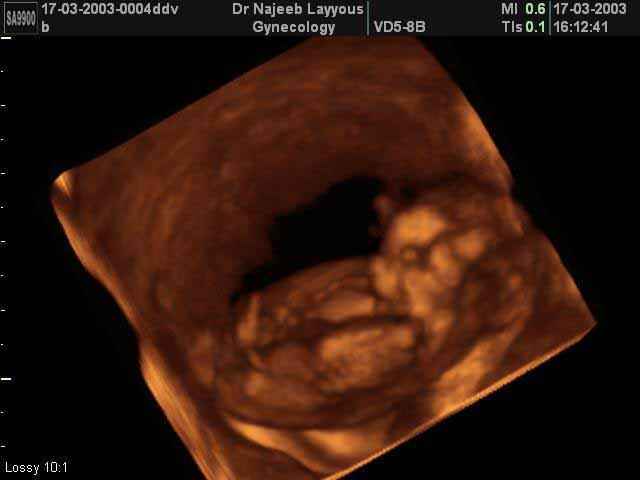

- First Trimester Ultrasound Photos

3D First Trimester Ultrasound Scan Photos ( Early Pregnancy Ultrasound Photos ) | Dr N Layyous